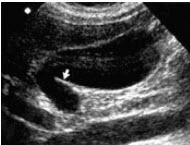

18、单项选择题

女性,5岁,超声检查如图所示,最可能的诊断是()